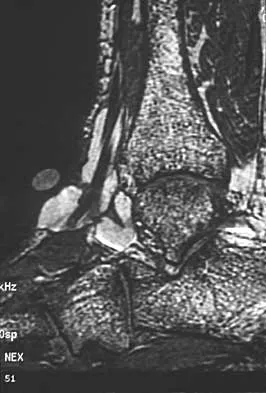

An 8-year-old boy with severe hemophilia A (factor VIII) and no inhibitor is averaging eight transfusions per month for bleeding into the right ankle. Examination shows synovial hypertrophy; range of motion consists of 0 degrees of dorsiflexion and 20 degrees of plantar flexion. The patient's knees, elbows, and left ankle have no restriction of motion. Standing radiographs of the right ankle are shown in Figure 18. Management should consist of

The patient has bilateral hypertrophic synovitis that is causing repeated hemarthroses and progressive arthropathy. Ankle synovectomy in patients with hemophilia is effective in significantly reducing the rate of joint bleeding and in slowing the progression of the arthropathy; therefore, bilateral synovectomies is the treatment of choice. Range of motion can be effectively maintained after ankle synovectomy. Bracing and prophylactic transfusions would be ineffective at this time. Ankle arthrodesis should be reserved for patients with severe pain. Compared with patients who have juvenile rheumatoid arthritis, patients with hemophilia generally do not have involvement of the subtalar joint and rarely require a pantalar arthrodesis. Greene WB: Synovectomy of the ankle for hemophilic arthropathy. J Bone Joint Surg Am 1994;76:812-819.